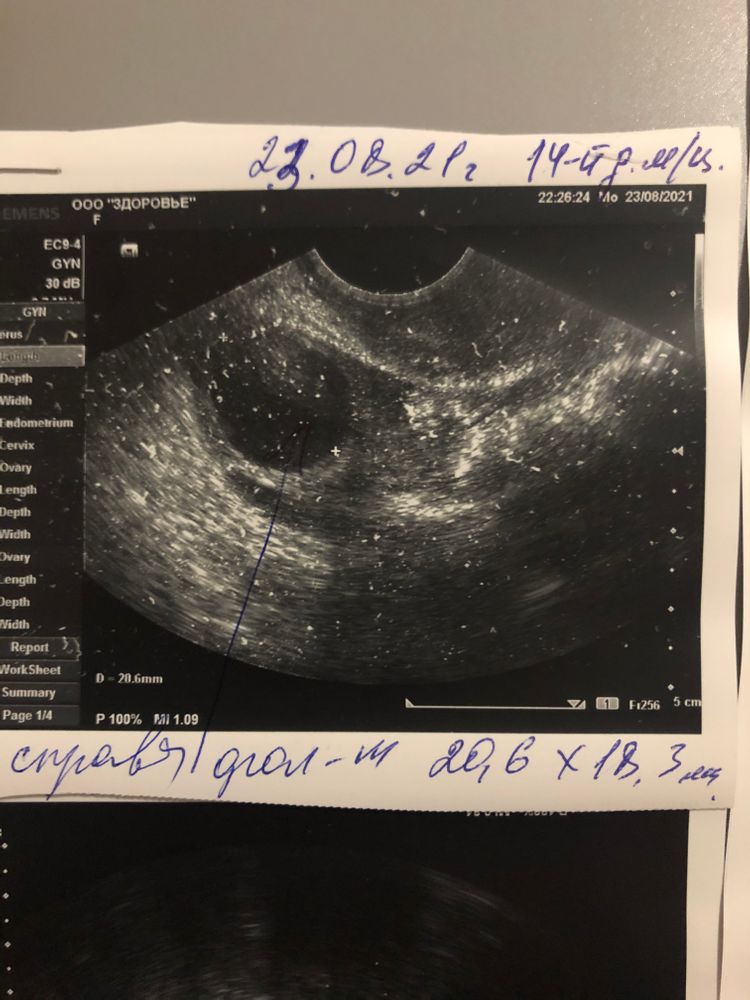

Я вижу большой ДФ - чёткие контуры и чёрный внутри. ЖТ с размытыми контурами и серой взвесью внутри.

Tina, предпоследнее фото. Написано, доминантный фолликул 20,6 на 18,3 мм. Он уже мог в тот же день совулировать кстати.